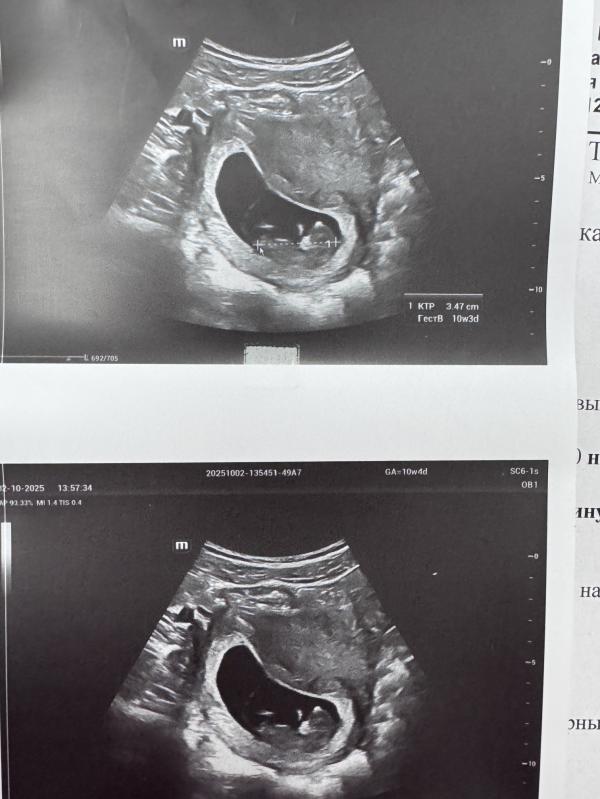

Завтра 10н5д иду вставать на учет 🥰